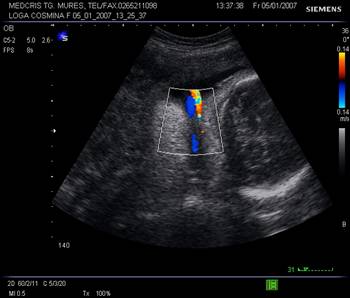

Fig. nr.222. Hematom

la nivelul placii deciduale a

placentatiei la 10 sapt. , cu intreruperea vascularizatiei la Doppler color (

sageata ). Se remarca vascularizatia cordonului ombilical si insertia centrala

a acestuia in placenta